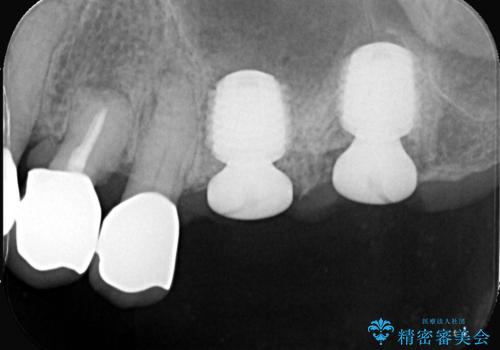

- 左上6番と7番の奥歯に、それぞれ遠心分岐部病変と頬側分岐部に10mmの深い歯周ポケットを認め、慢性的な炎症があります。再根管治療後も経過観察を続けましたが、病状の改善や歯周組織の付着が見られず、外科的歯内療法も選択肢にはありましたが、予後が不確実であること、そして患者様の負担を最小限に抑えたいというご意向を受け、抜歯即時埋入インプラントによる治療計画を立案しました。通常1年ほどかかる治療期間を大幅に短縮し、3ヶ月での機能回復を目指します。

今回のケースでは、特に難しいとされる奥歯の抜歯即時インプラントを適用しました。まず、炎症を起こしていた左上6番と7番を慎重に抜歯し、その直後にインプラントを埋入。この抜歯即時埋入により、歯を失ってからインプラントを埋入するまでの期間を省くことができ、骨の吸収を最小限に抑えられました。痛みや腫れもほとんどなく、患者様は「思ったより楽だった」と仰っていました。結果的に、通常であれば1年近く要する治療をわずか3ヶ月で完了。機能性と審美性を兼ね備えた新しい奥歯により、快適な食生活と笑顔を取り戻していただけました。